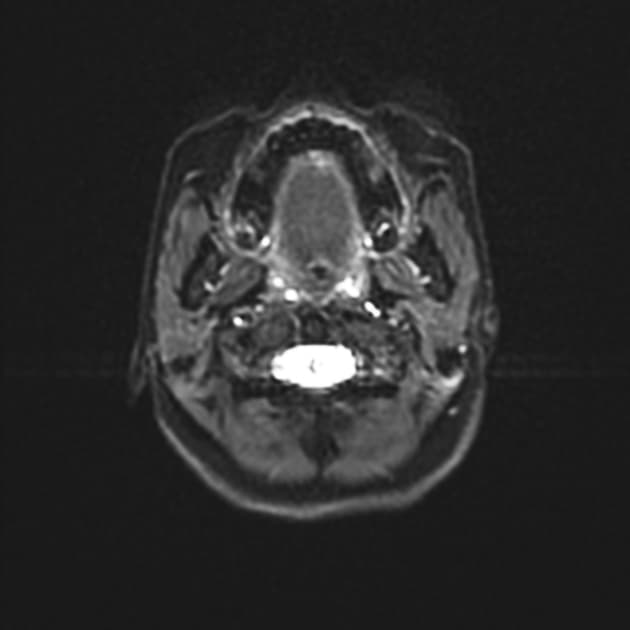

- Tổn thương dạng khối nang ở thùy thái dương trước bên phải (right anterior temporal lobe cystic mass lesion) được ghi nhận, trên cộng hưởng từ cho thấy tín hiệu giảm ở chuỗi xung T1, tăng tín hiệu ở T2, viền giảm tín hiệu trên mọi chuỗi xung.

- Tổn thương cho thấy hạn chế khuếch tán (restricted diffusion) với tín hiệu tăng trên hình ảnh khuếch tán (DWI) và tín hiệu giảm trên bản đồ ADC.

- Tổn thương có ngấm thuốc viền (rim enhancement) sau tiêm thuốc cản quang.

- Phổ cộng hưởng từ (MR spectroscopy) của tổn thương thùy thái dương phải cho thấy đỉnh lipid/lactate tăng rõ rệt, đồng thời giảm N-acetyl aspartate (NAA), creatine (Cr) và choline (Cho). Vùng não lân cận có phổ cộng hưởng từ chủ yếu bình thường, chỉ tăng nhẹ choline.

- Tổn thương được bao quanh bởi phù vận mạch (vasogenic edema), gây xóa (effacement) các rãnh vỏ não tương ứng và chèn ép nhẹ sừng thái dương của não thất bên phải.

- Ghi nhận dày lên và ngấm thuốc của màng não (meninges) kế cận.

- Xương sọ đáy cũng bất thường: giảm tín hiệu trên T1, tăng tín hiệu trên T2, ngấm thuốc không đồng nhất, gợi ý viêm xương (osteomyelitis).

Ca lâm sàng này minh họa một biến chứng nội sọ nghiêm trọng do viêm tai xương chũm và viêm xoang không được điều trị: viêm xương sọ đáy lan vào khoảng gian súc bên phải và hình thành áp xe thùy thái dương. Các hình ảnh học điển hình của áp xe mủ bao gồm tổn thương nang viền ngấm thuốc, hạn chế khuếch tán trên DWI/ADC, phù vận mạch xung quanh và phổ cộng hưởng từ cho thấy đỉnh lipid/lactate tăng cao, giảm NAA, Cr và Cho. Dày màng não và thay đổi tín hiệu tủy xương sọ đáy kèm ngấm thuốc không đồng nhất xác nhận chẩn đoán viêm xương. Tình trạng này, đôi khi được gọi là 'viêm tắc tĩnh mạch nhiễm trùng nguồn gốc tai' hoặc 'hội chứng Gradenigo' khi tổn thương đỉnh đá, cần được chẩn đoán sớm và điều trị tích cực bằng kháng sinh đường tĩnh mạch, đôi khi cần dẫn lưu phẫu thuật. Các chẩn đoán phân biệt bao gồm các tổn thương ác tính như u nguyên bào thần kinh đệm hoặc di căn hoại tử trung tâm, và ung thư màng não kèm nhiễm trùng. Việc kết hợp lâm sàng với sốt, chảy dịch tai và rối loạn dây thần kinh sọ (ví dụ: đau mặt do tổn thương dây V) là rất quan trọng.